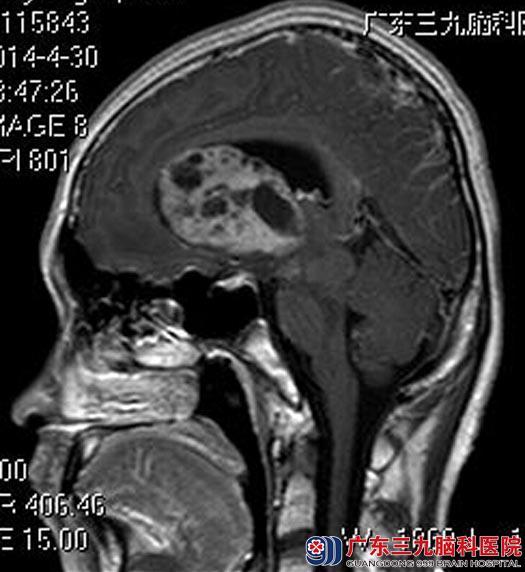

“才头痛一周时间而已,怎么就长肿瘤了?”父母将信将疑地带着小杨来到广东三九脑科医院。头颅MRI检查提示:左侧基底节区示一团块状占位病灶,累及脑桥左侧、中脑左侧,病灶范围约48.0mm×59.6mm×39.3mm,占位效应明显,左侧侧脑室受压,中线结构明显右偏。幕上脑室系统明显扩大,并周围间质性水肿信号,考虑生殖细胞瘤可能性大。

完善相关检查后,鲁明主任主刀,在全麻下行左侧额叶、脑室内肿瘤切除术,术中见灰白色肿瘤组织,质软,血供丰富,予超声刀逐步切除肿瘤,手术顺利。术后病理结果:生殖细胞瘤。

▲术前